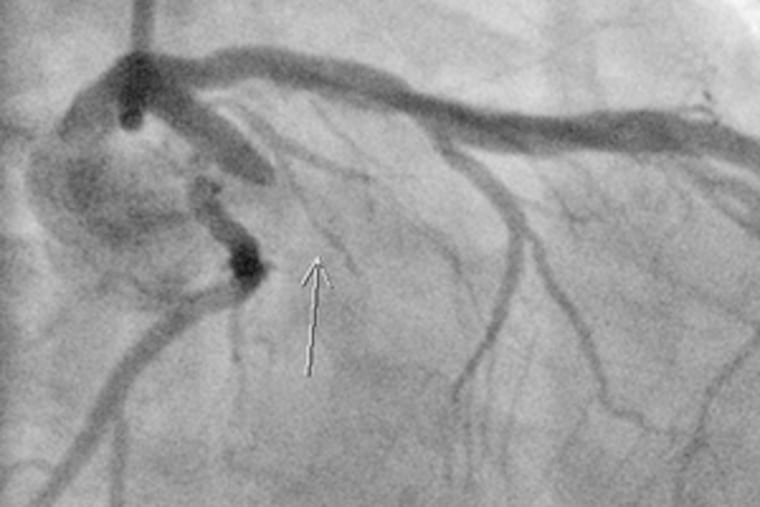

In angioplasty procedures, a catheter is threaded through an artery from a small incision usually near the groin up to the blockage. There, a balloon is inflated to restore blood flow. Often a stent - a small wire-mesh scaffold - is used to prop the blood vessel open.

Once there, he put on scrubs and rushed to the cath lab. Seventy-nine minutes after the patient arrived in the ER, Boyek and his team had inflated the balloon, placed two stents, and restored blood flow to his heart.